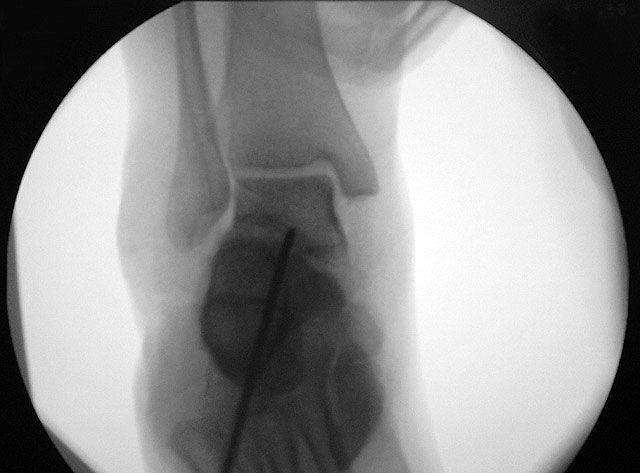

Abbildung 1

Abbildung 2

Ziel der Korrektur ist eine Reposition des Kalkaneus in eine physiologische 5° valgus Stellung. Eine Überkorrektur in Varus ist in jedem Fall zu vermeiden. Die Stellung wird anschließend mit K-Drähten fixiert, über die kanülierte Schrauben eingebracht werden können."> 155.</li>

Ziel der Korrektur ist eine Reposition des Kalkaneus in eine physiologische 5° valgus Stellung. Eine Überkorrektur in Varus ist in jedem Fall zu vermeiden. Die Stellung wird anschließend mit K-Drähten fixiert, über die kanülierte Schrauben eingebracht werden können." srcset="/assets/images/1/3-9tsh2b2m85xxjf3.jpg 1x, /assets/images/q/3-q5j2bj6y0h8725z.jpg 1.5x, /assets/images/k/3-h9kd23kj30b48p9.jpg 2x" width="270" height="240" loading="lazy">